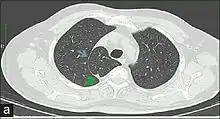

HRCT thorax, axial section delineates a well-defined, convex-shaped fold (Blue arrow), the azygos fissure. A tear-drop shaped density noted at the bottom of the fold (Green arrow) is the azygos vein.